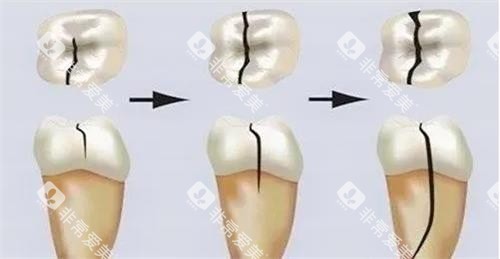

口腔检查:通过口镜、探针及X光片确定龋坏范围。

去除腐质:使用高速/低速牙钻或手工工具(如小刮匙)清除坏死牙体组织,保留健康牙体。

窝洞消毒:涂抹消毒剂(如氢氧化钙)杀灭细菌。

填充材料:

浅龋:单层树脂材料(130-300元)。

深龋:分层填充(底层氢氧化钙护髓,中间玻璃材料,外层树脂,300-1000元)。

调整抛光:修整外形,消除咬合高点,抛光表面。

关键点:若龋坏累及牙髓,需先根管治疗(费用增加至500-4000元)。